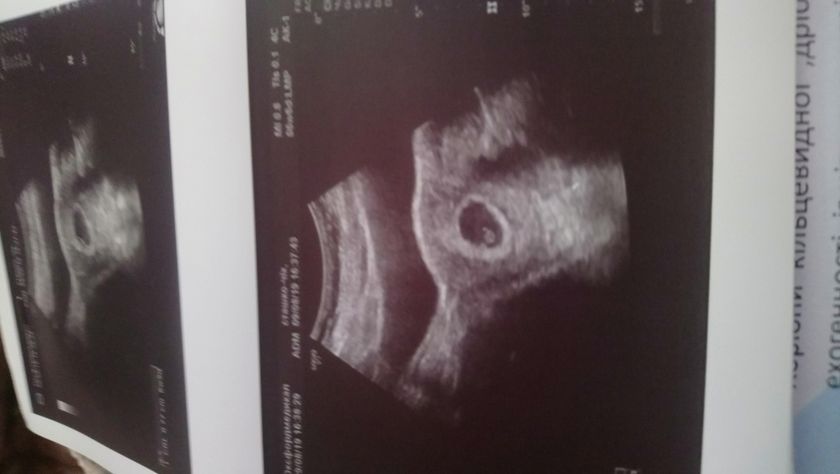

От мои размеры на 6 недель и 6 дней по изи(по месячным 7 недель) тоесть разница в один день.

ПЯ- 23мм

КТР- 7,7мм

ЖМ- 4 мм

СБ+

Гематом нет, угроз нет.

Заключение: прогресирующая беременность 7 недель.